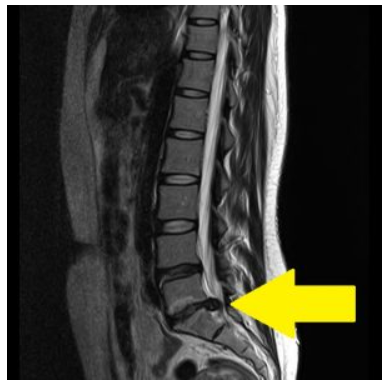

「病院でMRIを撮ったら“椎間板ヘルニアがあります”と言われました…」

実は、腰痛や痺れなどの症状が全くない健康な人でも、MRIを撮るとヘルニアのような所見が映ることが多いのをご存じでしょうか?

健康な人でもヘルニア所見は珍しくない

代表的な報告としては、米国整形外科学会誌や放射線学会誌にまとめられた Brinjikjiら(2015年, AJNR)による大規模レビュー(3,110人, 33研究) があります。

つまり、「MRIに映っている=必ず症状の原因」ではないということです。